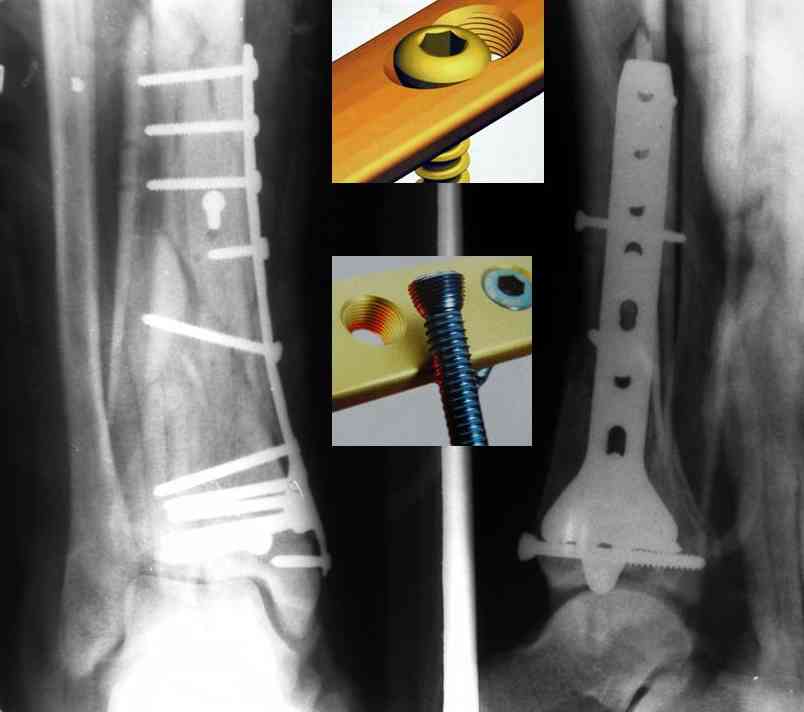

Посылаю результат лечения предыдущего больного через год.

С уважением Дрягин

Кстати, при переломах переднего края по классификации АО В-3 при переломах пилона пластина укладывается по передней поверхности. Она достаточно тонкая и эластичная, не надо этого бояться. Посылаю три снимка.